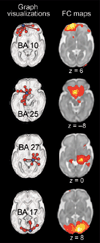

Compelling evidence indicates that psychiatric and developmental disorders are generally caused by disruptions in the functional connectivity (FC) of brain networks. Events occurring during development, and in particular during fetal life, have been implicated in the genesis of such disorders. However, the developmental timetable for the emergence of neural FC during human fetal life is unknown. We present the results of resting-state functional magnetic resonance imaging performed in 25 healthy human fetuses in the second and third trimesters of pregnancy (24 to 38 weeks of gestation). We report the presence of bilateral fetal brain FC and regional and age-related variation in FC. Significant bilateral connectivity was evident in half of the 42 areas tested, and the strength of FC between homologous cortical brain regions increased with advancing gestational age. We also observed medial to lateral gradients in fetal functional brain connectivity. These findings improve understanding of human fetal central nervous system development and provide a basis for examining the role of insults during fetal life in the subsequent development of disorders in neural FC.